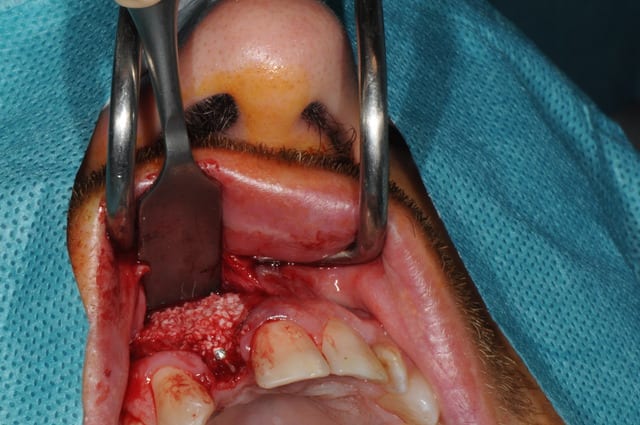

Salut, voila les photos de la chirurgie. rien d'extraordinaire , mais si certains ont des conseils, je suis preneur, j'ai la même chose à faire samedi matin

Pourriez vous me dire ce que vous utilisez pour éroder le mur palatin et éviter un axe trop vestibulaire?